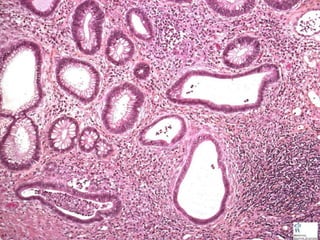

OTHER MÜLLERIAN

• ENDOMETRIOD, malignant

– (looks like endometrium)

OTHER MÜLLERIAN •ENDOMETRIOD, malignant – (looks like endometrium) • CLEAR CELL, malignant – (clear cells, reminiscent of renal clear cell ca.) • CYSTADENOFIBROMA, benign – (BENIGN “FIBROUS” COMPONENT) • BRENNER TUMOR, benign – (transitional cell nests) • CARCINOMA with SARCOMA – (adenosarcoma, mixed Müllerian)